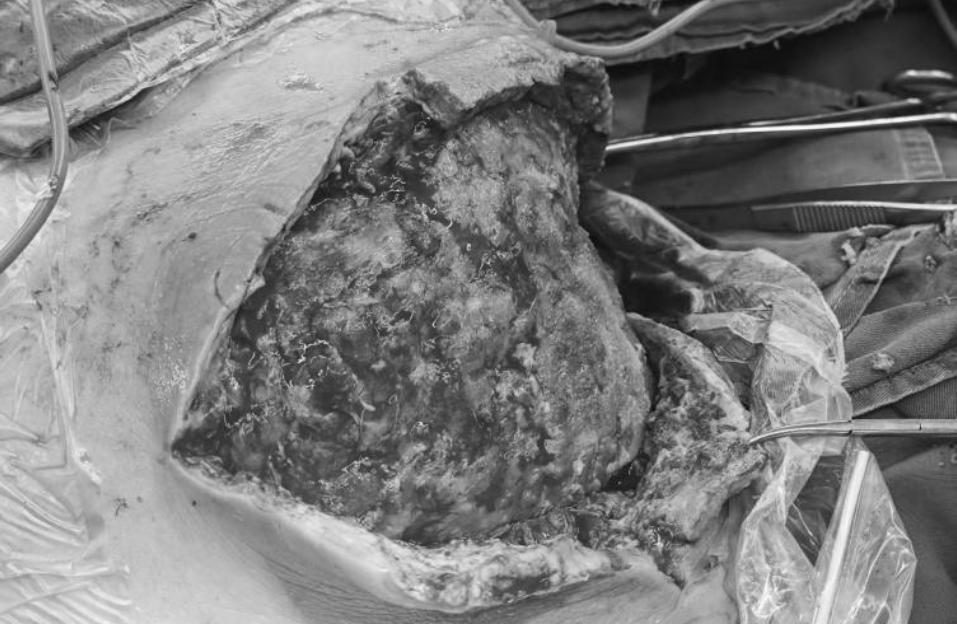

这位患者来院时面色苍白,颈部肿胀,用手捂着患处,步履蹒跚地走进我院烧伤整形科诊室。医生判断:这是坏死性筋膜炎!这个起病急、进展快、致死率极高的“隐形杀手“,正以惊人的速度吞噬着她的生命。

坏死性筋膜炎是一种罕见的侵袭性软组织感染,通常由细菌外毒素产生造成破坏。该病起病急骤,进展迅速,常伴有全身性中毒症状和多器官功能障碍,临床预后极差,病死率可高达30%以上,是外科领域最具挑战性的急危重症之一。

而患者的处境可谓雪上加霜——她不仅患有多年糖尿病,血糖长期失控,还伴有精神疾病,治疗配合度较差。检查显示,感染已悄然逼近胸膜,穿刺抽出的脓液混杂着血丝,血培养结果证实为金黄色葡萄球菌感染。患者随时可能休克、多器官衰竭,生命悬于一线!“启动全院MDT会诊!”医院立即启动多学科诊疗(MDT)机制,烧伤整形科、重症医学科、感染性疾病科、麻醉科、心胸外科、耳鼻咽喉科、神经内科等多学科专家迅速集结,协同制定治疗方案。

第一次手术:创面清创+负压封闭引流术

第二次手术:创面清创、扩创术缝合术+任意皮瓣转移术+负压封闭引流术

第三次手术:创面清创、扩创+2%取皮术+自体中厚皮移植术

经过一个多月的全力救治,患者的感染完全控制,创面完全愈合,终于平安出院,重获新生!